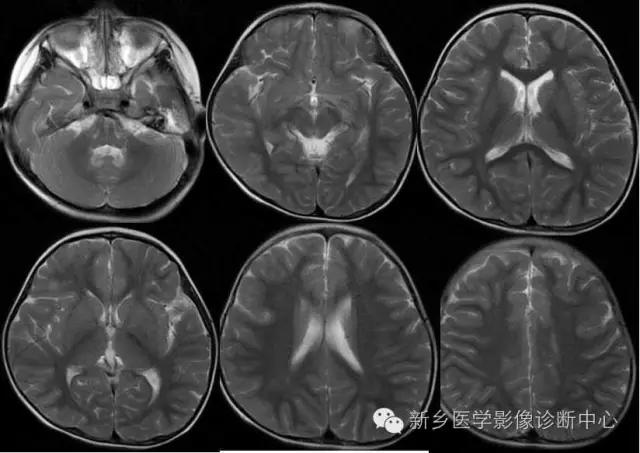

---III期:后期婴儿阶段:出生后6~12个月

此时,白质内的水分逐渐下降,并有髓鞘形成,小脑半球、以至小脑叶、内囊全部、大脑枕叶、顶叶后部和额叶相继髓鞘形成和部分成熟。

---IV期:早期儿童阶段:出生后1~3年

>12个月~ 18个月 94% 属此期;

>18个月- <2岁100% 属此期。T2WI观察

亦称灰白质信号倒转期。随月龄增长大脑深部白质内水分降低,水分比灰质少,外围区皮质逐渐变薄,白质信号区逐渐扩大。此期中间区(白质)呈低信号,灰质与中央区呈中等信号。